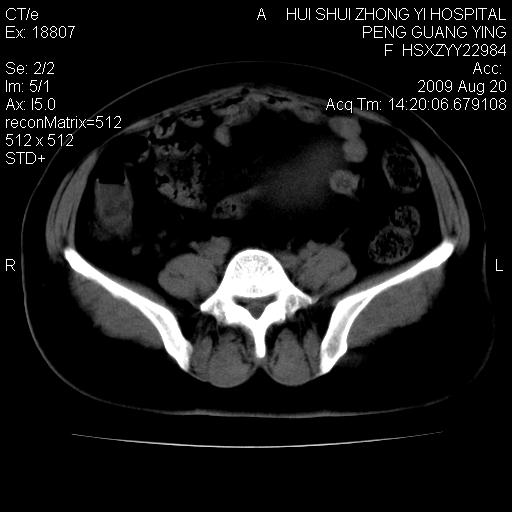

标题: CT21707:女,42岁,因发现下腹部包块2月。 [打印本页]

标题: CT21707:女,42岁,因发现下腹部包块2月。

病灶来源——子宫?附件?

从平扫角度看本人还是倾向于子宫肌瘤诊断,宫腔少量积液。

目前的影像表现显示肿块位于腹腔及盆腔,但具体定位,分清来源较困难,是否来源于卵巢、子宫无法定论,子宫直肠及子宫膀胱周围脂肪间隙尚较清晰,如果患者有过腹腔好或者盆腔手术史,也可以形成不典型的血中,最好手术后定为定性,我期待结果。

软组织密度,与子宫一致。双侧卵巢形态、密度好,不支持来源于卵巢。

病史不全面,病灶来源可能是子宫或卵巢,若临床有剖腹产、痛经史,则更支持前者,亦更支持子宫腺肌症